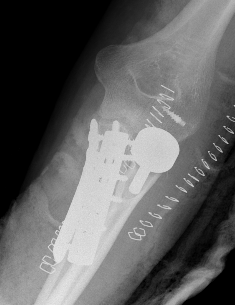

Olecranon plate + ORIF Type II coronoid process + radial head replacement

Olecranon plate with radial head replacement

Olecranon plate with radial head replacement + LCL repair

Olecranon plate + medial coronoid buttress plate + radial head replacement